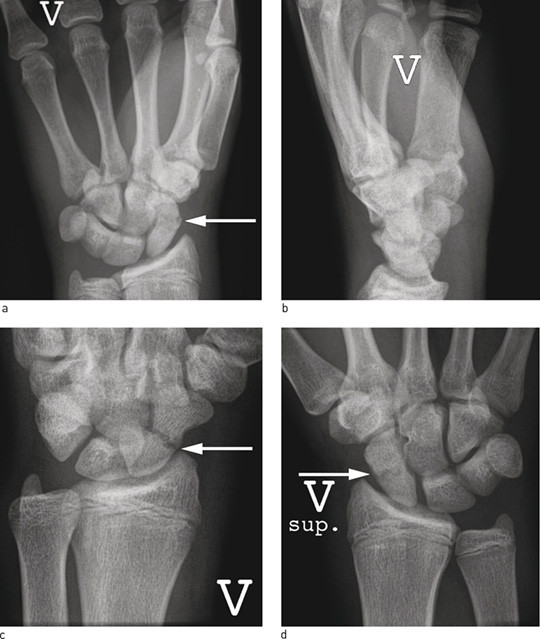

Figure 5  Treatment of scaphoid pseudarthrosis. a) 18-month old scaphoid pseudarthrosis (white arrow) in young man, b)…

Figure 5 Treatment of scaphoid pseudarthrosis. a) 18-month old scaphoid pseudarthrosis (white arrow) in young man, b) Operated with bone graft from crista and 1.6 mm smooth metal pins. Post-operative picture with cast, arrow on bone graft, c) Final check-up after 14 months. Normal wrist function, no secondary wrist arthrosis, bone graft incorporated in scaphoid